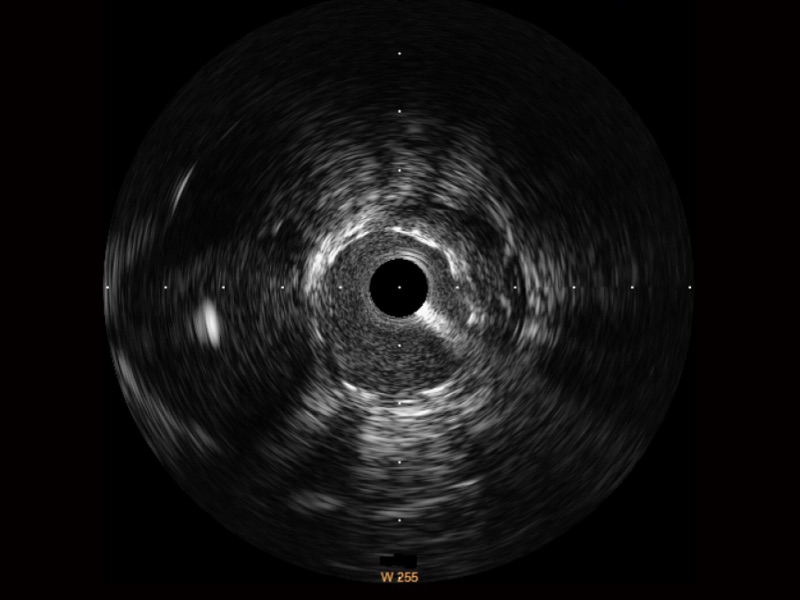

• 美狮贵宾会官网宽频IVUS图像

• 传统IVUS图像

对比传统IVUS导管成像,美狮贵宾会官网宽频IVUS图像的近场支架梁显影更细腻,远场中膜外血管仍清晰可辨,兼顾远中近,兼顾分辨力与穿透深度